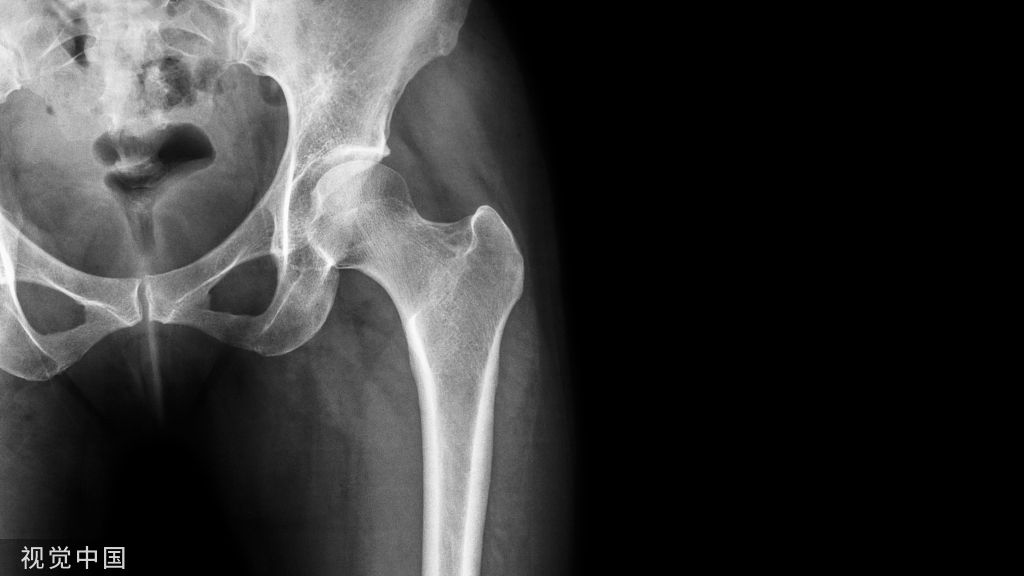

成骨不全症 (脆骨病)

成骨不全症(Osteogenesis imperfecta),又称成骨不全、脆骨病、先天性发育不全、瓷娃娃、原发性骨脆症,是一种罕见遗传性骨疾病。